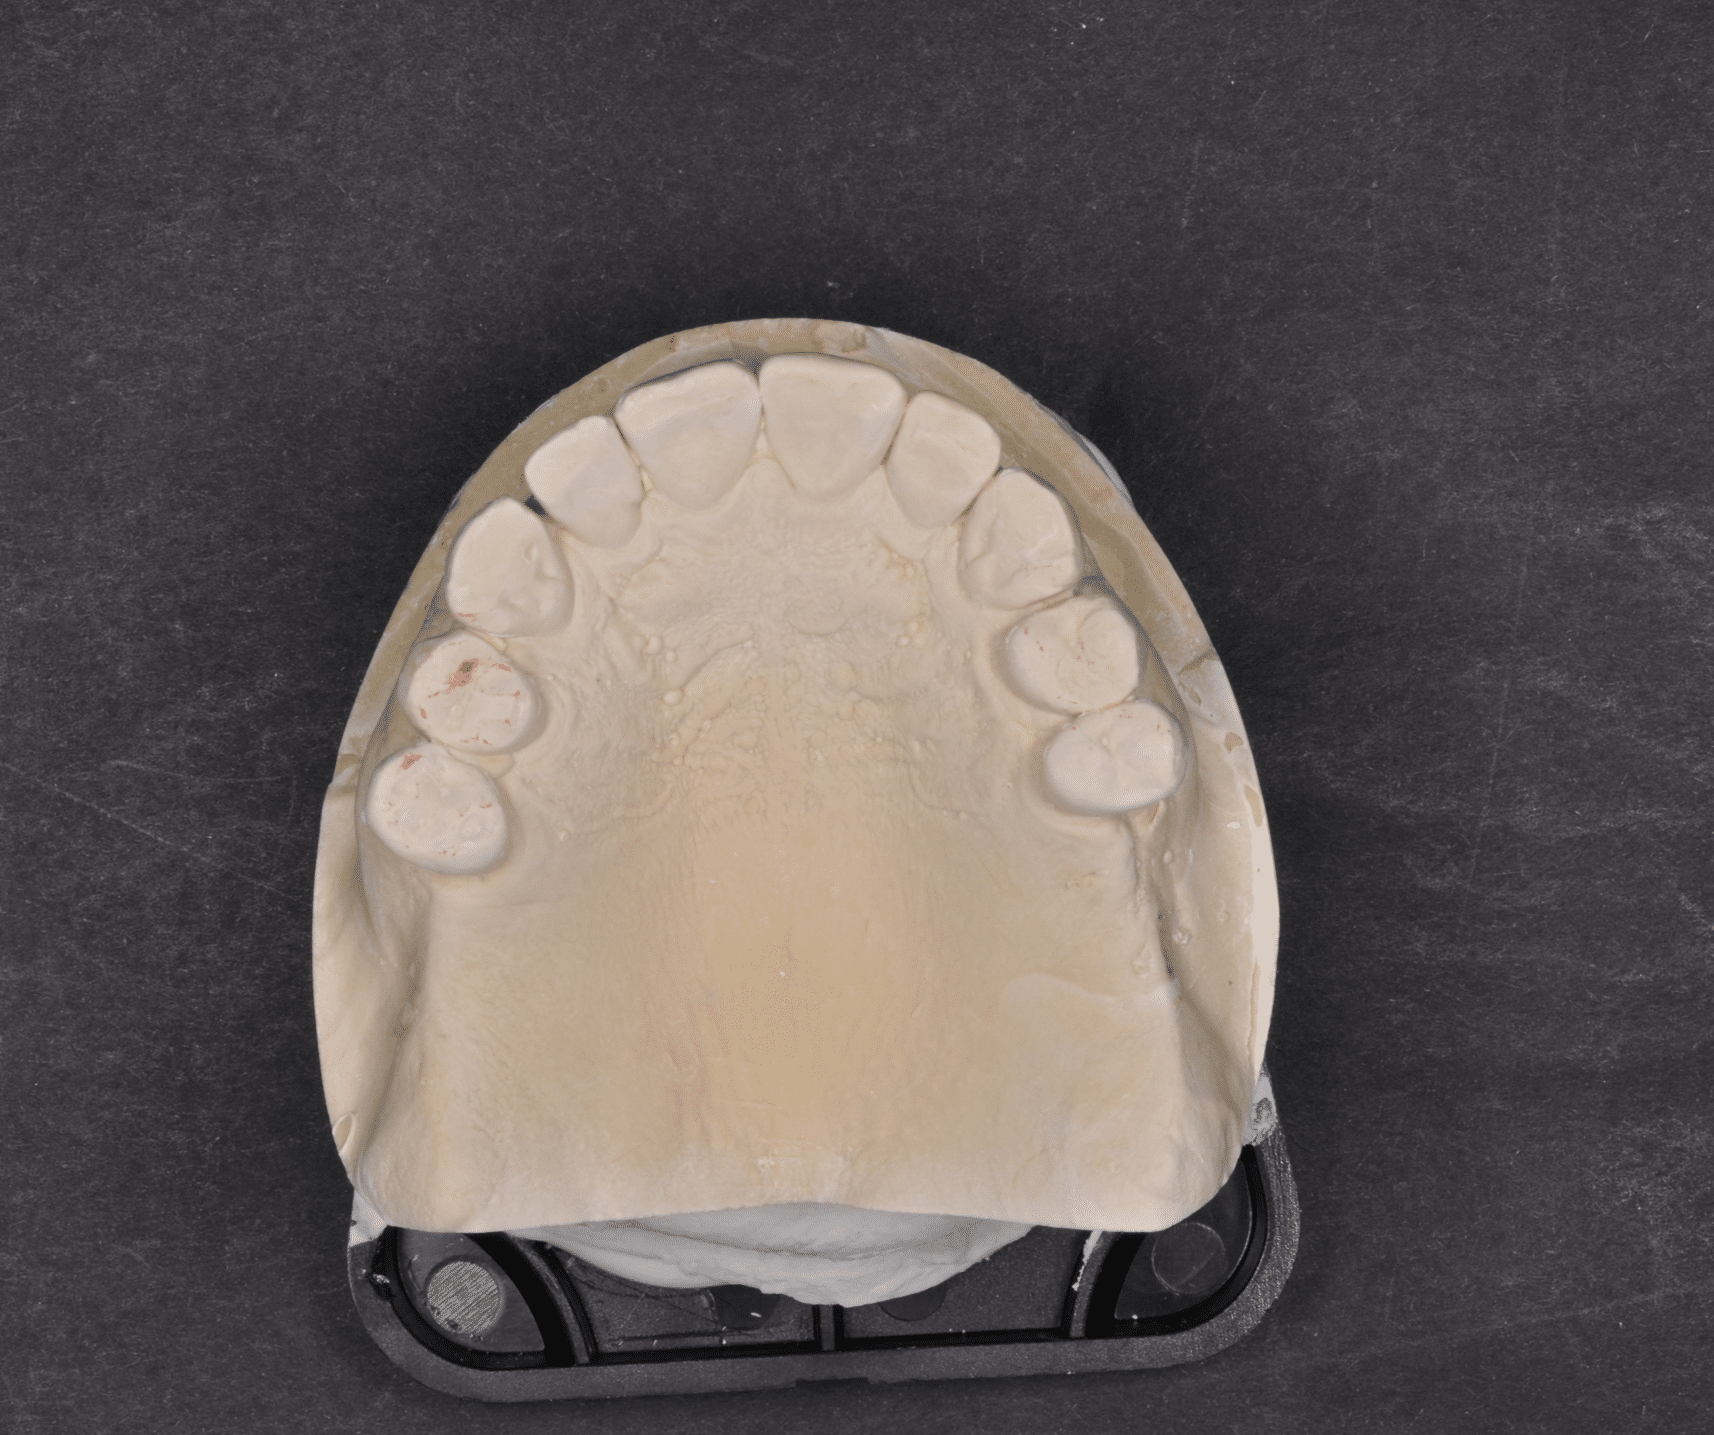

Împreună cu pacientul, am optat pentru inserarea implantelor cu ajutorul ghidului chirurgical pentru a plasa implantul în poziția protetică ideală și pentru a permite realizarea coroanelor insurubate pe implant. A fost efectuată scanarea digitală a arcadelor și a ocluziei pacientului, iar împreună cu tehnicianul radiolog de la DigiRay a fost suprapus fișierul .stl al amprentei digitale peste fișierul .dcm de la CBCT, utilizând software-ul 3Shape.

S-a planificat individual poziția și axul de inserție al fiecărui implant.